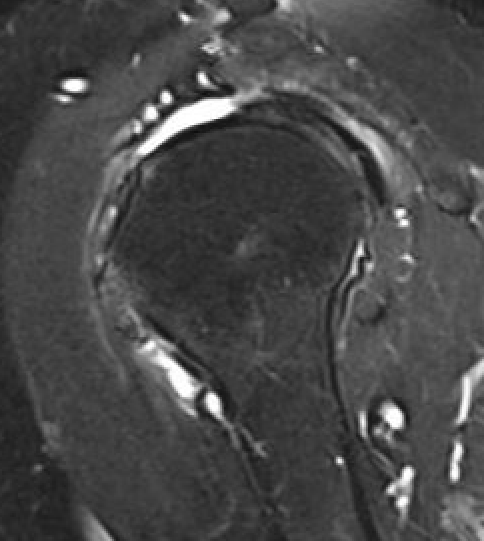

Full thickness rotator cuff tears

Partial bursal sided tear Partial articular sided tears

Subscapularis tears

Small full thickness rotator cuff tear of supraspinatus - retracted to footprint

Large full thickness tear of supraspinatus and infraspinatus tendon - retracted to midhumeral head

Massive rotator cuff tear of the supraspinatus and infraspinatus tendon - retracted to glenoid